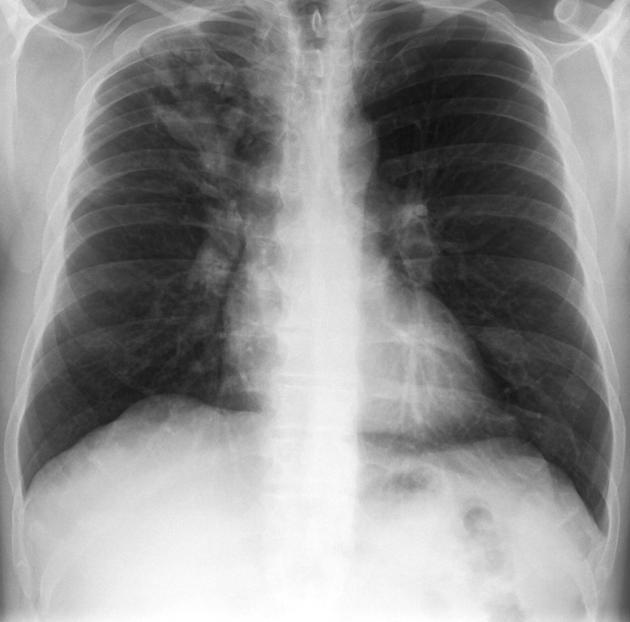

AIDS patient. Diagnosis?

Other imaging appearances?

Pneumocystis pneumonia. An opportunistic infection caused by Pneumocystis jiroveci. Most common in AIDS patients with profound T-cell immunosuppression, less commonly seen in patients with other forms of immunosuppression.

Imaging appearance: Ground-glass opacities in the parahilar regions and upper lobes. Severe cases may present with dense air-space consolidation. If there is interlobular septal thickening, can have crazy-paving pattern. May develop pulmonary cysts (risk of spontaneous pneumothorax). Chest x-ray can be normal. Pleural effusion and LAD uncommon.